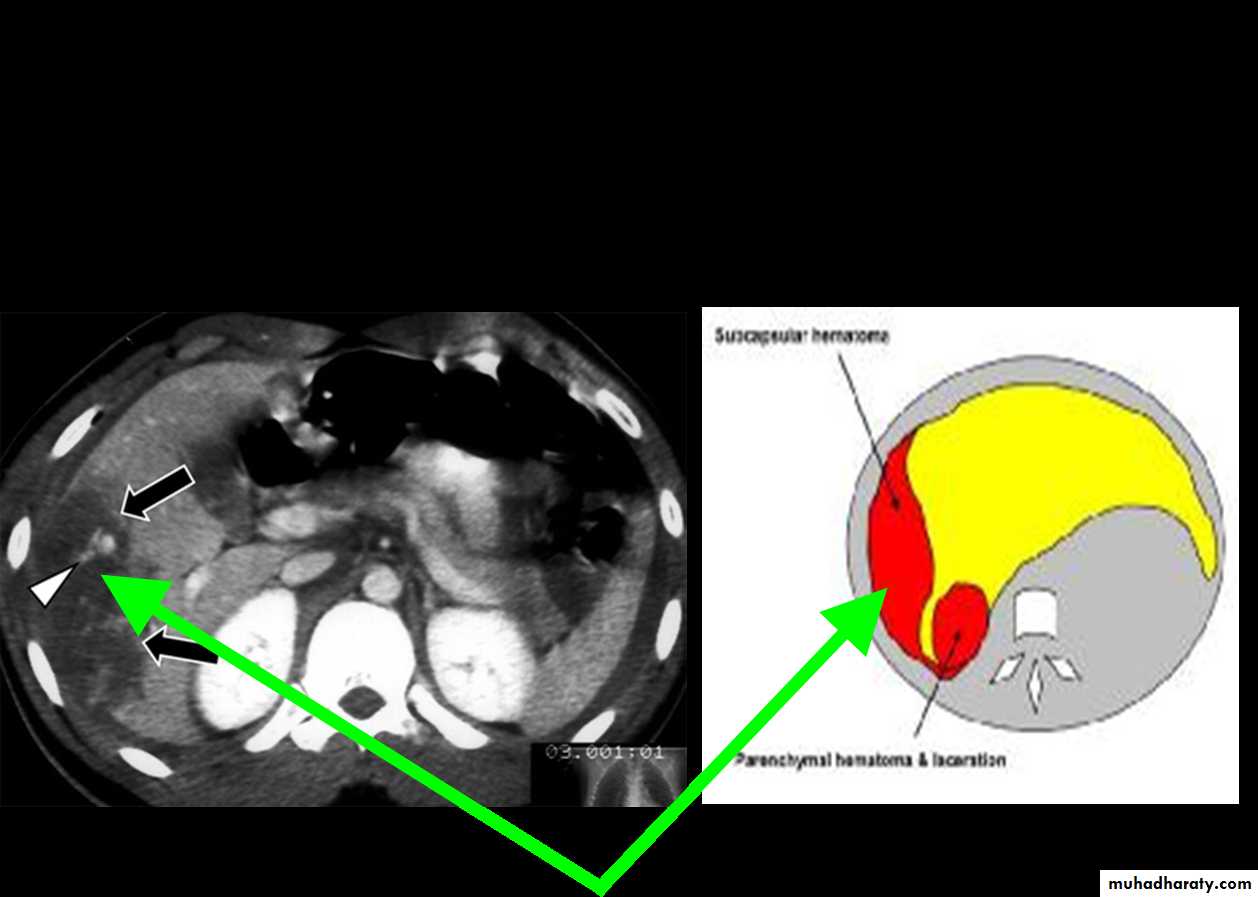

CT Scans

Accurate in localizing the site of liver injury and any associated injuries

Used to monitor healing

CT criteria for staging liver trauma uses AAST liver injury scaleGrades 1-6

Subcapsular hematoma

Laceration

Hepatic vascular disruption